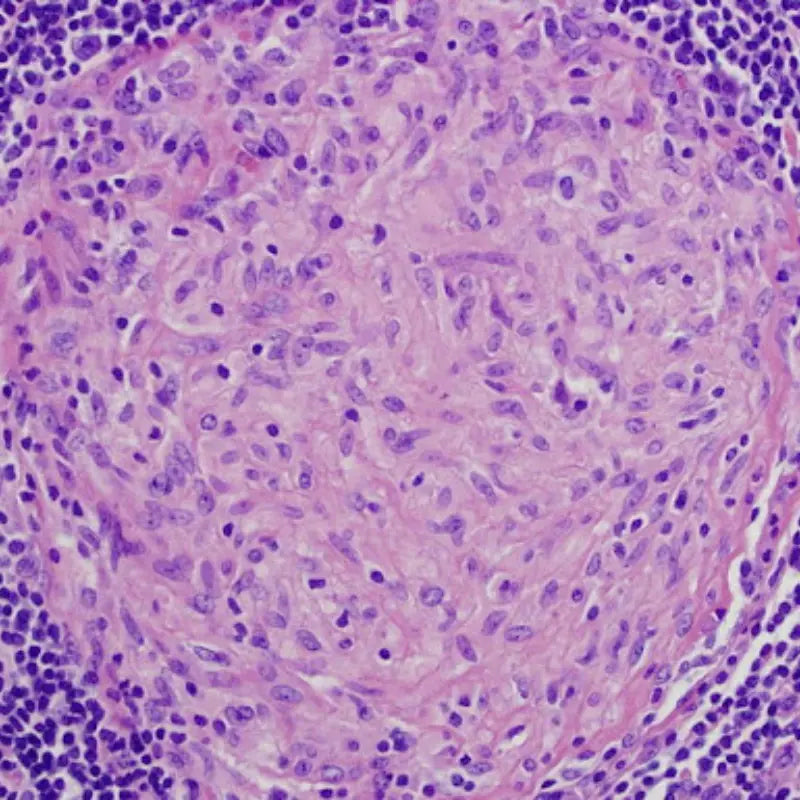

Image Credit: Sanjay Mukhopadhyay. Public domain.

3. Inflammaging

Inflammaging combines two terms: inflammation and aging. It describes how chronic, systemic inflammation that occurs in the absence of infection contributes to aging. For example, chronic inflammation damages tissues and increases the risk of age-related diseases in dogs.